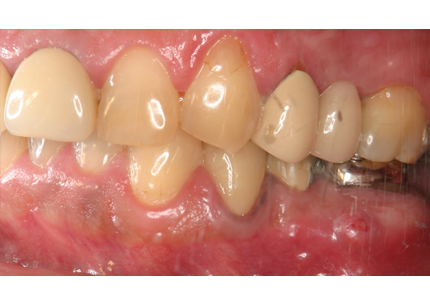

3.前回治療後5年経過(2021年2月)

【左下ブリッジ5番6番歯根破折の為要抜歯】

【左下5番ソケットシールドテクニック】

【ソケットシールドテクニックにて頬側骨の形態を維持する (右の様な骨のへこみを作らない)】

※ 通常、ソケットシールドテクニックは前歯部領域に用いるが小臼歯部でも採用しました

4.左下5番ソケットシールドテクニック

5.インプラント埋入(2021年6月)

8.補綴物完成(埋入後5か月)

9.左下3本最終補綴装着(2021年11月)

10.口腔内写真(2022年2月)

特に問題無く経過はとても良いです。

患者様ご本人も「良く咬めてとても良い」と満足されています。

11.口腔内写真(2025年6月)

右下2本初診より9年経過、左下3本埋入後4年経過、ともに経過良好。